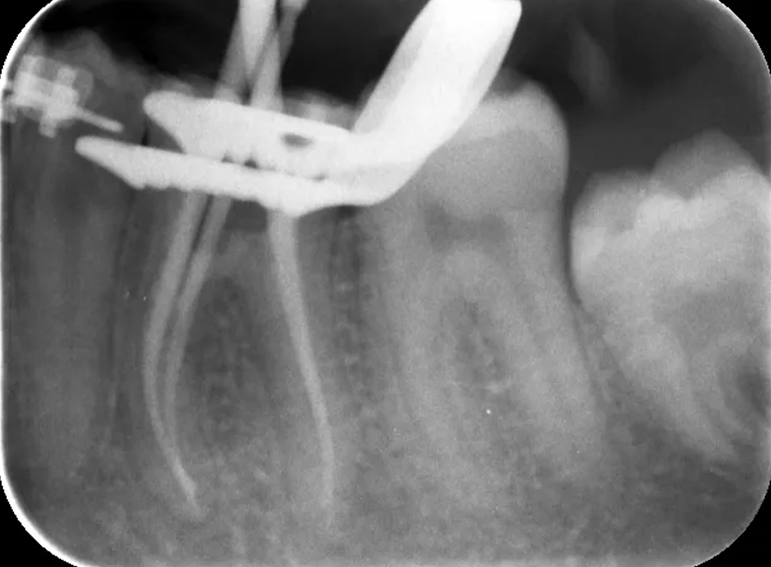

Root filling revision of a lower molar.